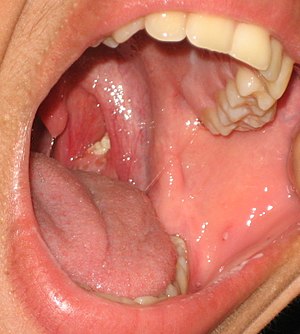

편도결석은 구강 내 편도에 생기는 작고 하얀 알갱이를 말합니다. 마치 치즈처럼 끈적끈적하고 고약한 냄새를 풍기는 것이 특징입니다. 오늘은 편도결석에 대해 원인, 증상, 치료법에 대해 알아보겠습니다.

편도결석은 편도선에 생기는 작은 이물질로, 주로 음식물 찌꺼기와 세균이 뭉쳐서 형성되는 쌀알 크기의 노란색 또는 흰색 덩어리입니다. 편도선은 면역 체계의 일부로, 우리 몸을 방어하는 역할을 하지만, 때때로 이곳에 이물질이 쌓이게 되면 편도결석이 생기게 됩니다.